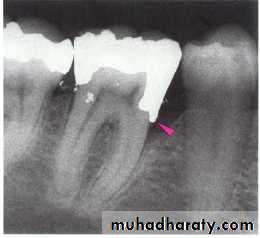

• Overhanging margins induce plaque accumulation & change

• the environment that allows growth of pathogenic bacteria &

• inhibit patient access to remove plaque.

4- Inadequate marginal fitness of restoration.

Subgingival margins typically have a gap of 20 to 40 microns between the margin of the restoration and the unprepared tooth.